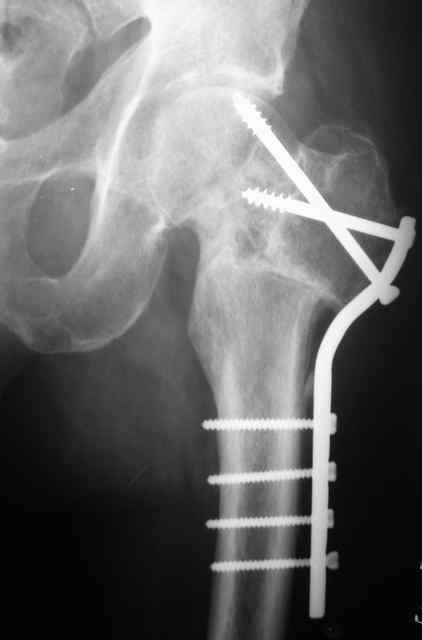

К сожалению, социальный статус пациента не восстановится ни после остеосинтеза, ни после ТЭП, в армии его уже не оставят. Склоняюсь к варианту медиализирующей остеотомии. С 90-х годов при недоступности основной массе платного эндопротезирования и невозможности три года ожидания квоты пациентам с несросшимися переломами ШБК мы делали вальгирующую чрезвертельную остетомию с медиализацией и пациенты вполне довольны результатами.Осложнения минимальны, начальные аваскулярные дистрофии головки способны к регрессу при соблюдении пациентом режима нагрузки. Очень привлекательно выглядит схема остеотомии с латерализацией удлиняющая шейку, описанная раннее на форуме Д.Кульджановым, но ее пока не выполняли.

Прилагаю снимок пациента 69 лет оперирован лет 8 назад.

Уважаемые коллеги! Отчитываюсь за проведенное вмешательство. Учитывая пожелания коллег и личный опыт решили ревизия места перелома с возможным последующим протезированием. При вскрытии места перелома - головка бедренной кости не жизнеспособна (не кровоточит), "костная пробка" на культе шейки бедренной кости. У тановлен эндопротез безцементной фиксации Stryker. Уважаемые коллеги большое спасибо за Ваши мысли и отзывы.